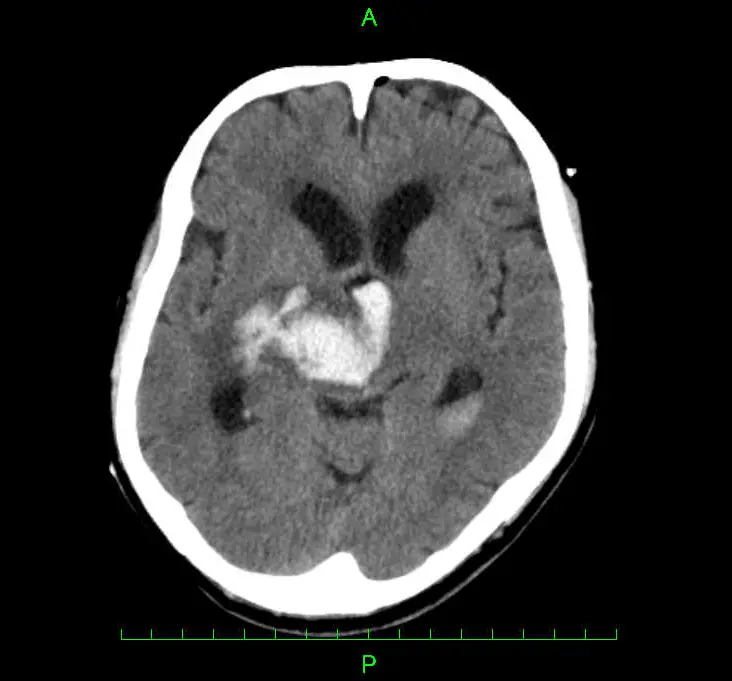

大脳や小脳、脳幹といった脳そのものの中で出血が起こり血腫(血のかたまり)ができることを脳出血(脳内出血)と言います。原因はほとんどが高血圧によるものですが、脳動脈瘤や脳動静脈奇形、脳腫瘍などによる場合もあります。出血が起きた脳の部位により大きく5つ(視床出血・被殻出血・小脳出血・脳幹出血・皮質下出血)に分類され、それぞれ異なる症状が出現します。なお、くも膜下出血は脳の外(表面)で出血が起きる病態のため、別のものとして分類されます。

主に頭部CT検査を用います。CT検査で脳出血と診断された場合は、出血原因の特定等を目的にMRI検査や造影検査などを行う場合があります。